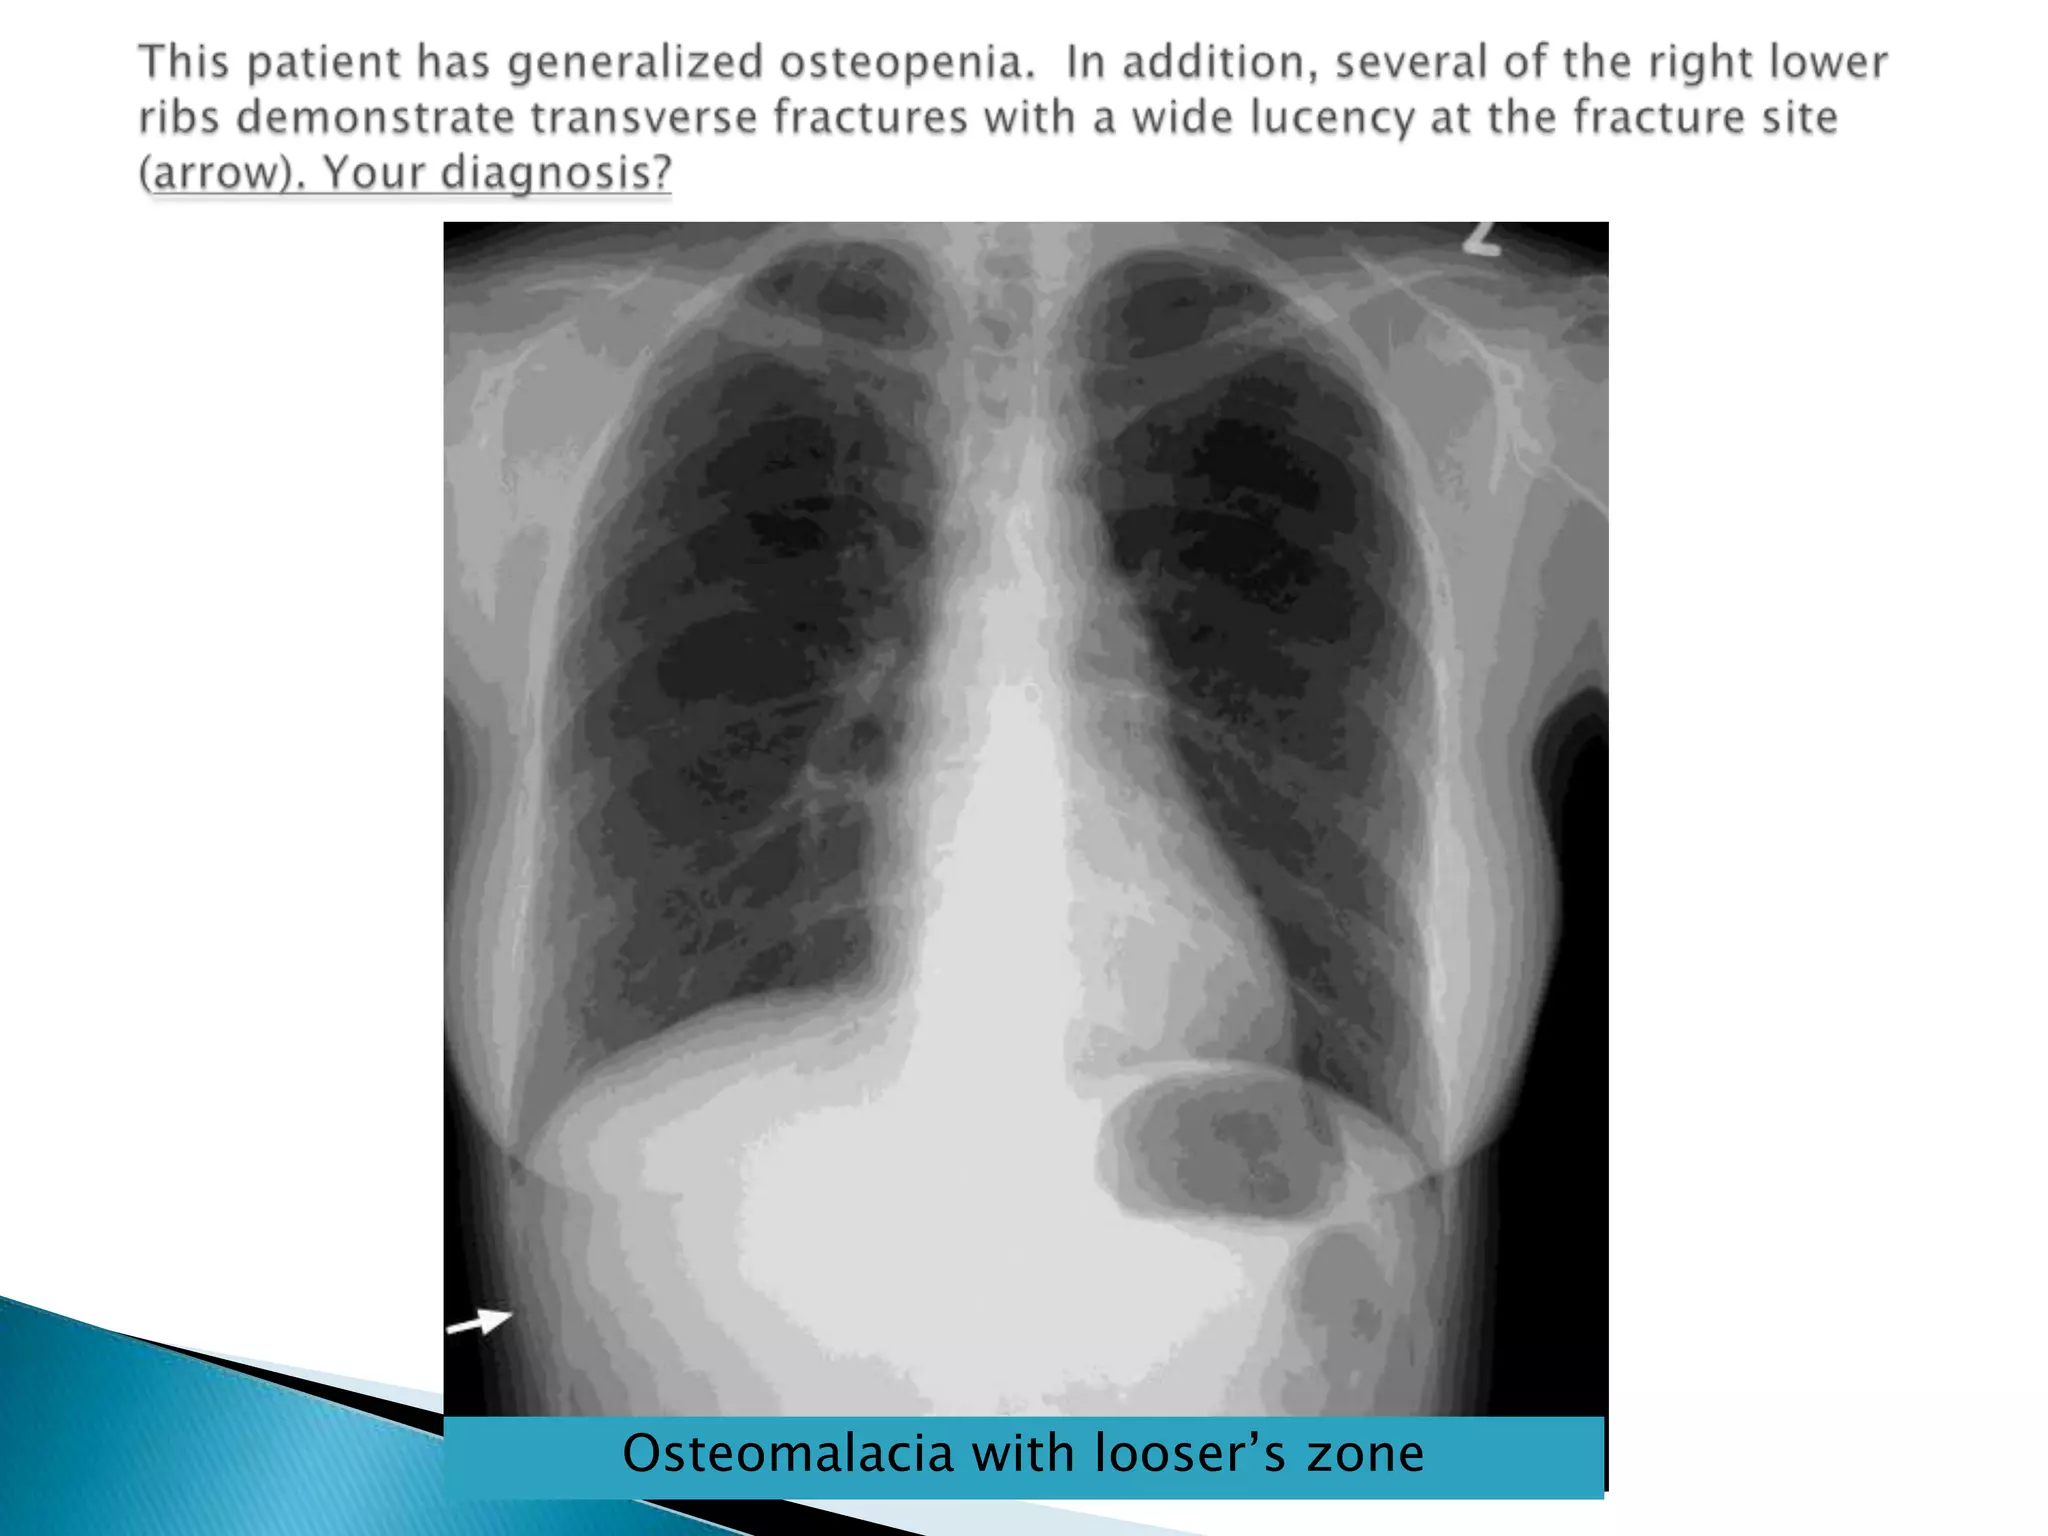

Radiological findings;Decreased bone density.Looser’s zones; are short lucent band running through the cortex at the Rt angles & may have sclerotic margin, commonest site are scapula, medial aspect of femurs,& pubic rami & ribsBone deformity due to bone softening e.g. biconcave vertebra bodiesosteomalacia

This patient has generalized osteopenia.  In addition, several of the right lower ribs demonstrate transverse fractures with a wide lucency at the fracture site (arrow). Your diagnosis?Osteomalacia with looser’s zone